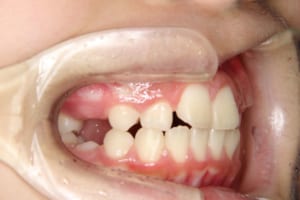

治療前

| 主訴 | 八重歯の生え方が気になる |

| その他/備考 | 上の犬歯が生えるためのスペースが全くない状態でした。放置すると重度の八重歯になることが想定されるケースです。 今回はあごの成長も利用しながら治療をするために、早めに後期治療(大人の矯正治療)に移行しました。 治療後レントゲン写真を見たところ、上顎前歯に若干の歯根吸収を認めました。 |